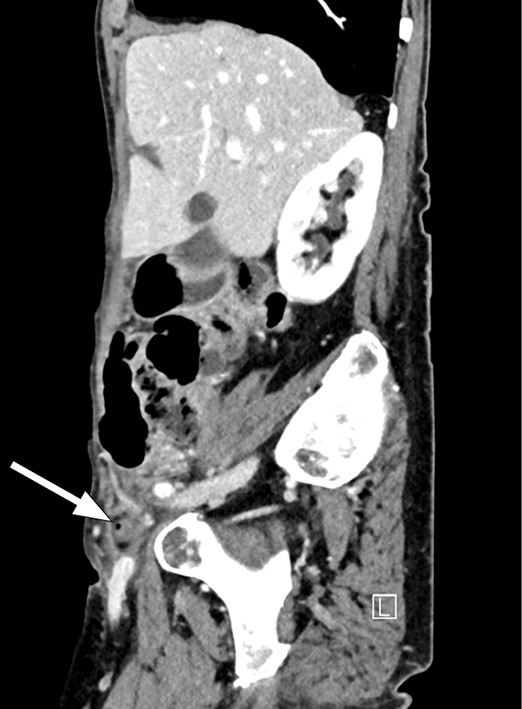

Grunnet mistanke om appendisitt ble det gjennomført CT abdomen med kontrast, der man så en tubulær struktur overfladisk i høyre fossa med tydelig omkringliggende fettvevsreaksjon inkludert fortykket peritoneum baktil. Det ble oppfattet som en inflammert appendiks og det var stedvis noe dårlig definert vegg som ga mistanke om perforert appendisitt. I tillegg så man en oppfylning i lyskekanalen på høyre side med en liten luftboble. Det var ingen sikker kommunikasjon til appendiks, men likevel sannsynlig at appendiks hadde herniert ned i femoralkanalen.

Tilstanden blir ofte diagnostisert peroperativt, men kan oppdages på CT abdomen i forkant. CT er den beste modaliteten for å fremstille de Garengeots hernie ved å kartlegge lokalisasjon og innhold i brokket. Femoralkanalen er medialt for femoralvenen og posterior for inguinalligamentet (1, 4).